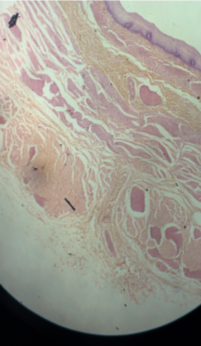

What is the black line pointing to? What is the overall picture?

-sebacous gland duct

-sectioned sebacious gland